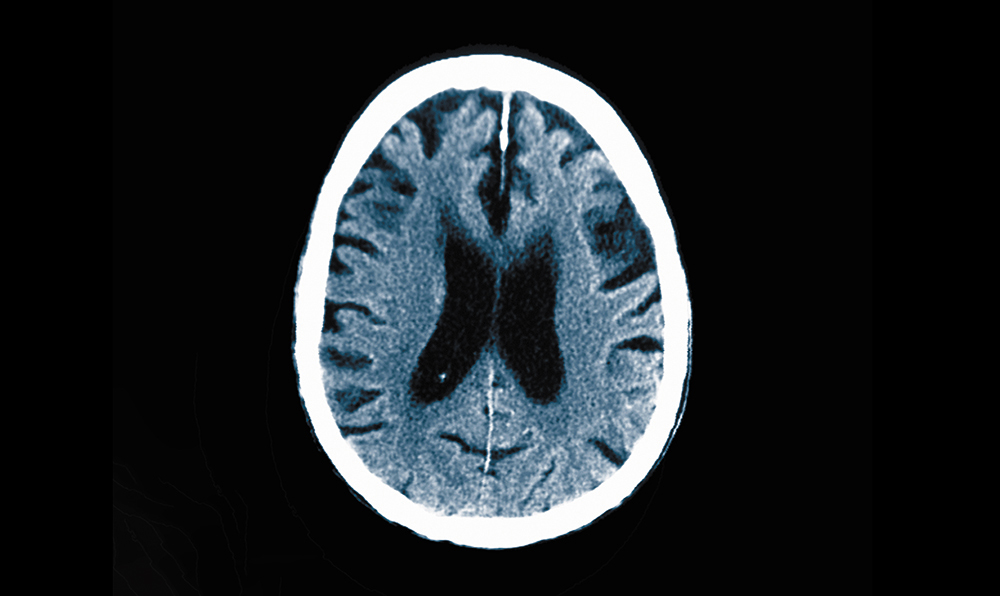

アルツハイマー病に侵された脳。 Credit: Callista Images/Image Source/Getty